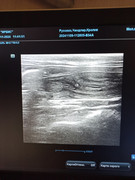

Сделали повторное узи 22.11. 2024 (первое было 09.11.2024). Высылаю фото и заключение.

Теперь ставят гидрометру и эндометрит. По мочевому мочекаменную.